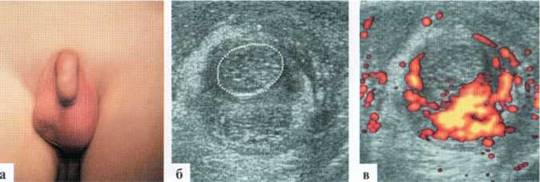

Трансформация гидатиды у детей является наиболее частой причиной развития СОМ. Причины возникновения этой патологии не всегда понятны, однозначного мнения о генезе заболевания в настоящий момент нет. Возможен как механический перекрут ножки гидатиды, так и ее инфаркт по невыясненным причинам. Гидатида значительно увеличивается в размерах, часто приобретает «ячеистую» структуру. Форма трансформированной гидатиды обычно округлая или овальная. Размеры чаще от 3x3 до 5x6 мм. При допплеровском исследовании трансформированная гидатита всегда аваскулярна (2.1.1).

Рис. 2.1.1. Трансформация гидатиды:

а — внешний вид пациента; б, в — гидатида (пунктир) у верхнего полюса яичка